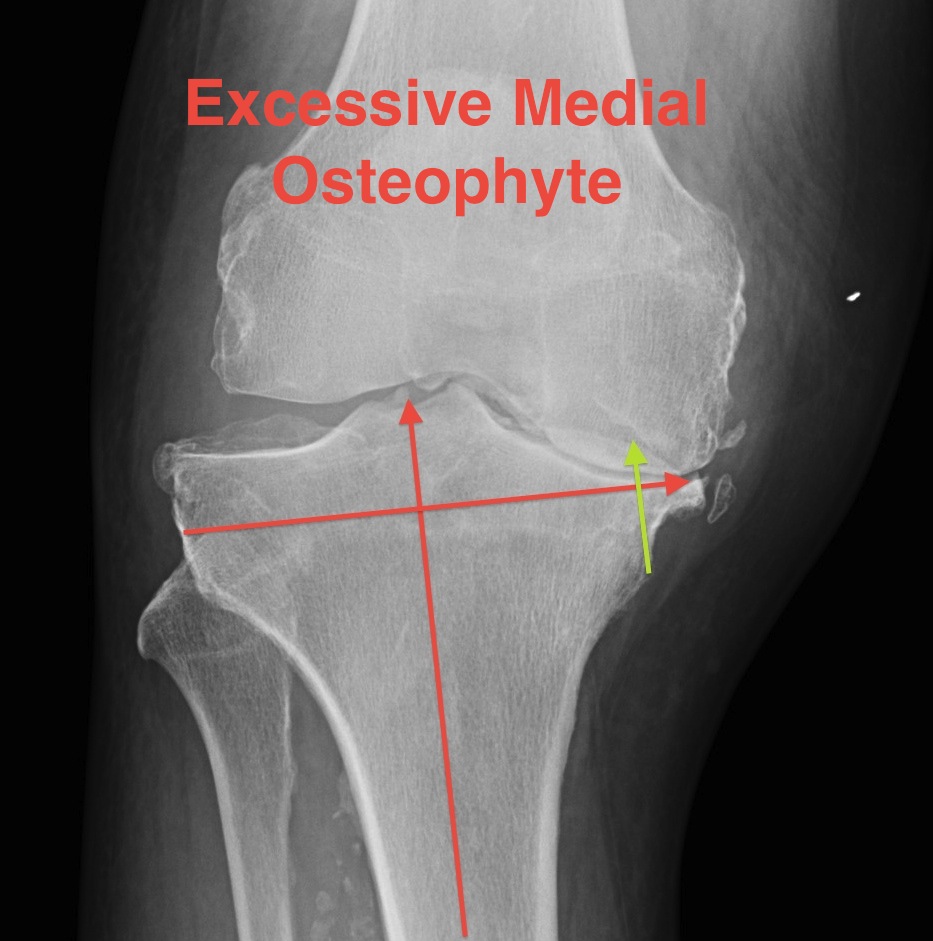

Removal ACL +/- PCL

Osteophytes debrided

Severe varus deformity

Problem

- 10 mm from lateral side does not take medial bone

- do not cut to level of medial defect as cancellous bone of the tibia becomes weak

Solution

- stay subchondral on lateral side

- never more than 10 mm cut lateral side

- build up medial side

Options

1. Cement

2. Autologous bone graft

- may have enough in primary

- from posterior or distal femoral condyles

- supplement with 2 screws

3. Augments

- 5 - 10 mm

- use stems if use augments

- offsets forces to the diaphysis (up to 30%)